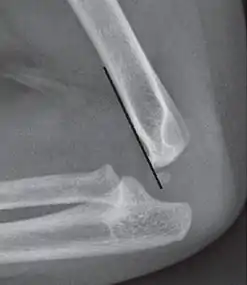

On lateral view of the elbow, there are five radiological features should be looked for: tear drop sign, anterior humeral line, coronoid line, fish-tail sign, and fat pad sign/sail sign (anterior and posterior).[3][8]

Anterior humeral line - It is a line drawn down along the front of the humerus on the lateral view and it should pass through the middle third of the capitulum of the humerus.[9] If it passes through the anterior third of the capitulum, it indicates the posterior displacement of distal fragment.[8]